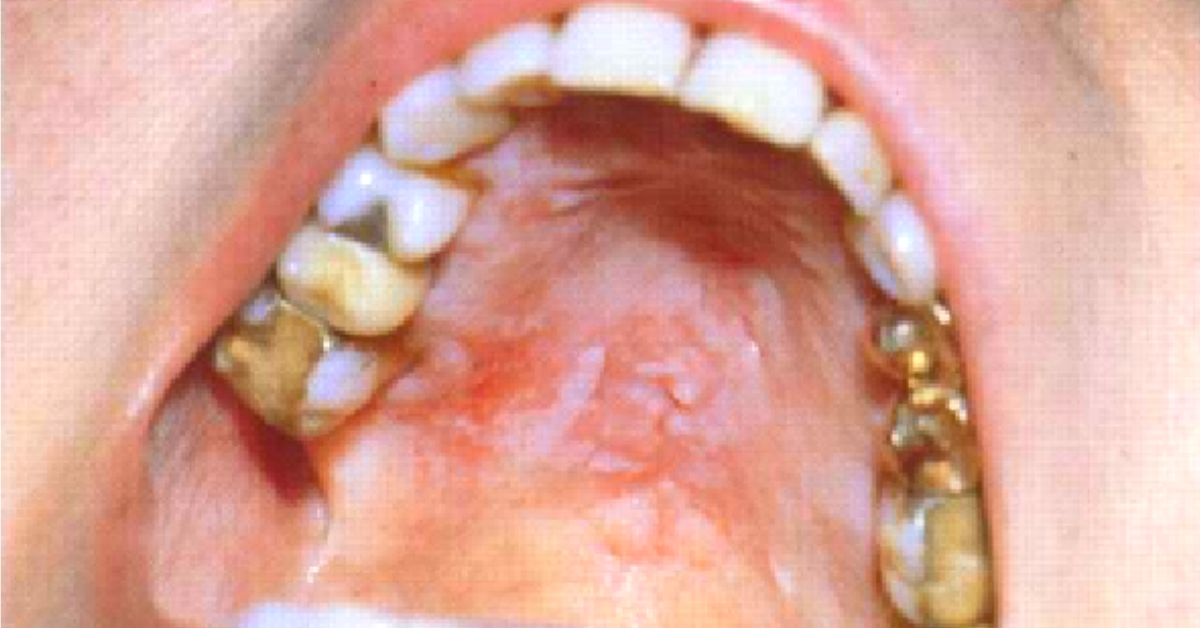

Hiperplasia Papilar del Paladar

Hiperplasia Papilar en Paladar

La hiperplasia papilar del paladar es una forma crónica rara de candidiasis que generalmente afecta a personas con paladar ojival que no usan dentaduras postizas.

Clínicamente aparecen múltiples nódulos esféricos pequeños en el paladar, que suele ser rojo. Esta lesión no debe confundirse con la estomatitis protésica, que aparece en personas que usan dentadura postiza.